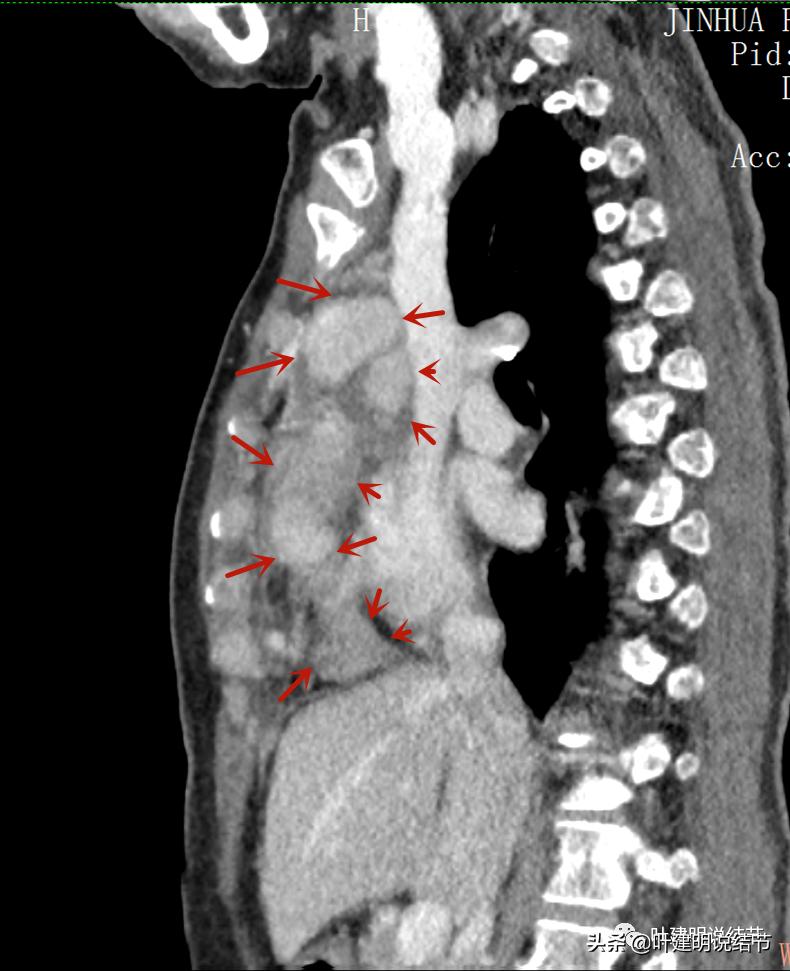

病灶之间似不相连的,矢状位上见从上到下延续的

近膈面病灶的轴位、冠状位与矢状位所见

病灶占据前纵隔从上到下全程,多中心,密度不均,对心脏与大血管有压迫,没有明显侵犯

病灶表面不平,中间有坏死